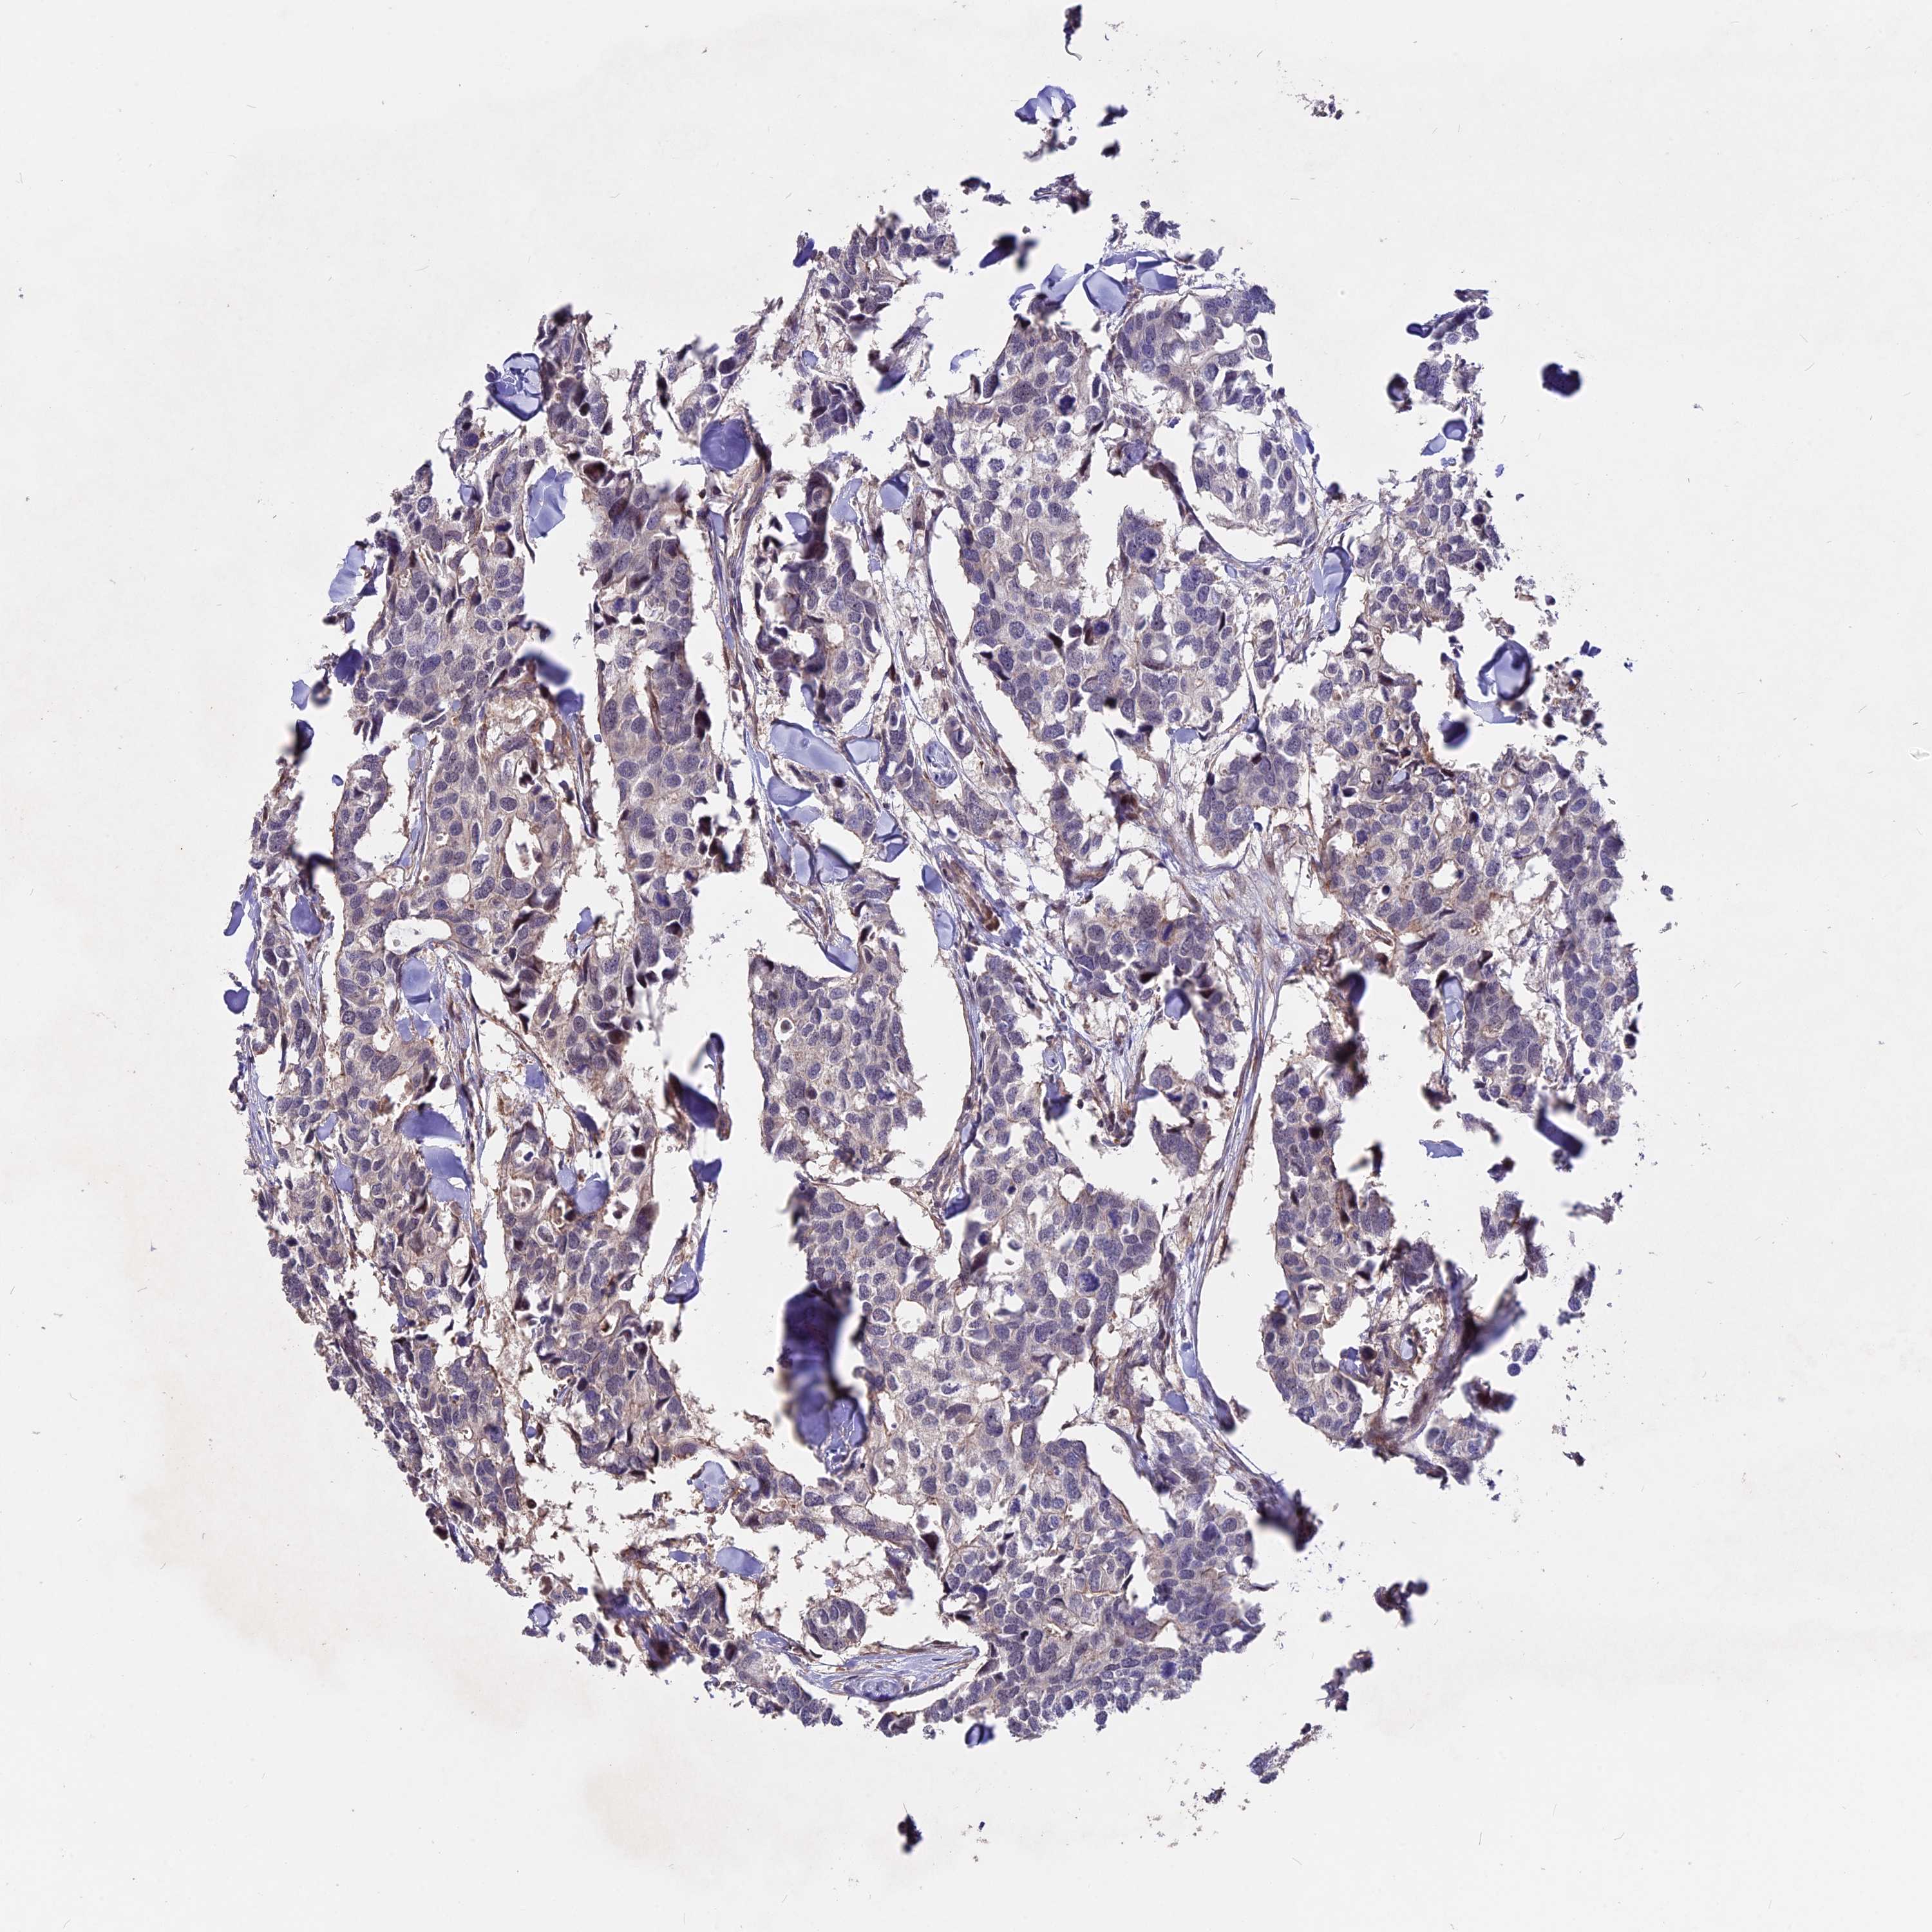

CANCER BREAST CANCER Show tissue menu

BRCA TCGA BRCA VALIDATION PROTEIN EXPRESSION

Breast cancer

Human cancer

Breast invasive carcinoma